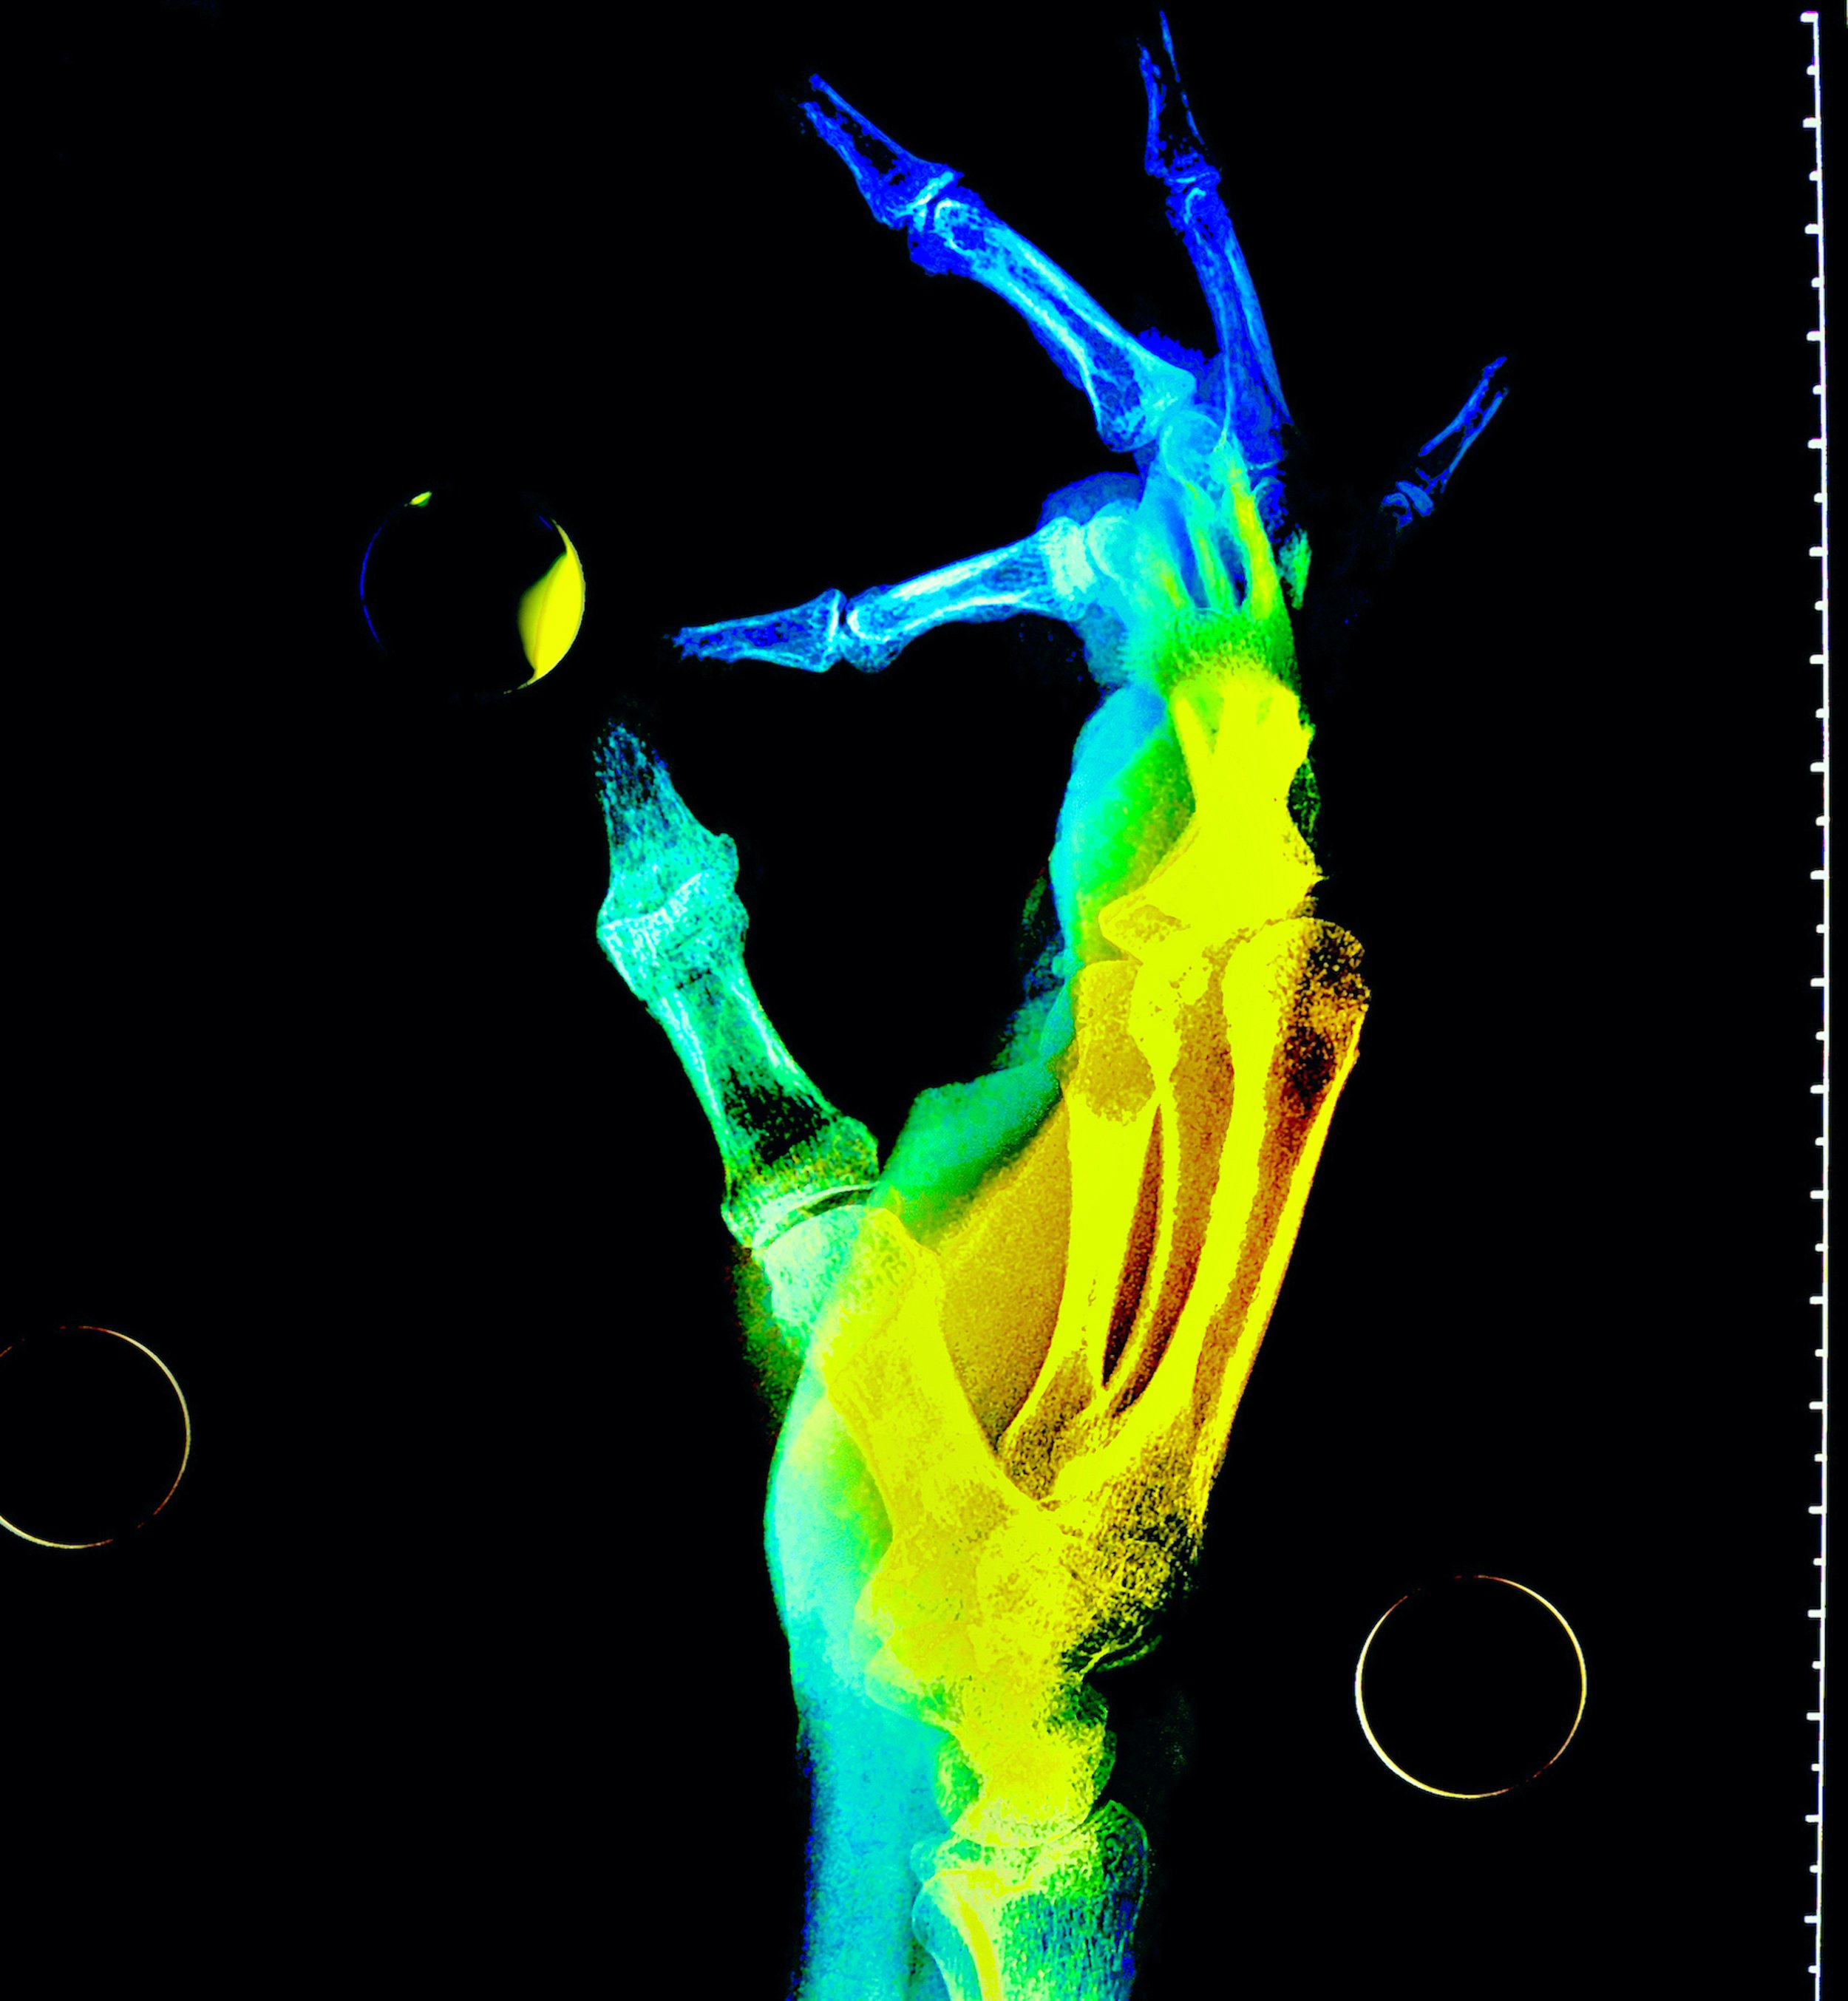

saturday night fever (boy meets girl diptych)

Selected for July/Aug 2022 exhibition in Art No.23’s Barcelona gallery.